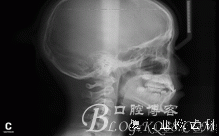

X線頭影測量值:SNA角77.13 ; SNB角75.73 ; ANB角1.41 ;SND角71.78 ;

U1toA-Pog 2.42 ;IMPA角96.48 ; FH-MP角26.37。

診 斷:安氏I類錯(cuò)合(III類傾向)。骨骼III類關(guān)系。凹面型:上頜劣生長、下頜過生長。上頜尖牙萌出間隙不足。前牙骨性反咬合。